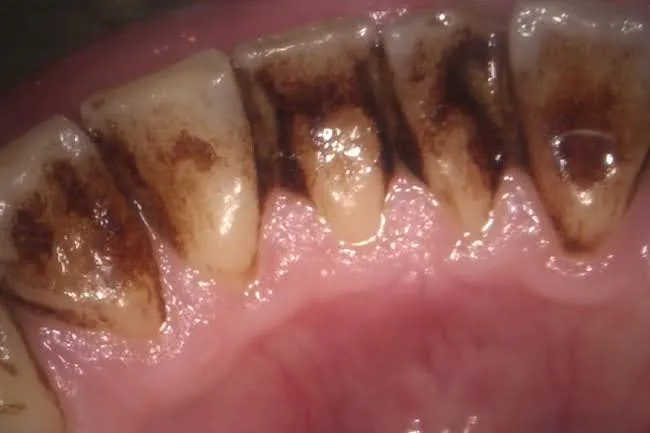

Case.1

Before

After

- 主訴

- 口臭がきになる

- 治療期間

- 1週間~

- 治療費

- 保険治療

- 治療内容

- 歯石の除去と機械的な歯面清掃

- 治療のリスク

-

- 術後の出血や痛みが出る可能性がある。

- 保険診療だと着色除去には限界がある。